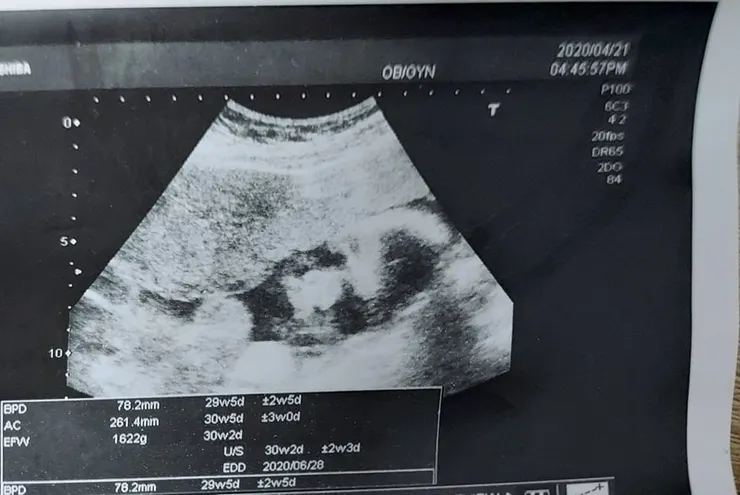

2020.4.17(五)PM1:44 (4.21 29w5D--1622G)

人生啊要進入八個月了,天啊!每次都很期待別人快卸貨,但是一點都不想趕快卸貨,想到要卸貨就想到,當天到底怎麼知道啊,會不會一邊破羊水一邊要走樓梯,怎麼去醫院,到底要痛多久才會生,到底多痛,想到生的時候是不是屎尿狂噴,還要被剪一刀,希望這個慘痛的時間可以趕快過去啊,我知道關關難過關關過,因為我以前工作的時候也是這種感覺,每次都會很擔心,但是按照時間的順序,很多事情還是會過去的女人本柔弱,但是為母則剛,但是我不要太剛,剛剛好就好。